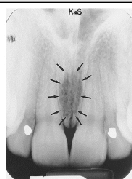

Incisive Foramen

small round radiolucent area between roots of max centrals

(radiolucent)

Superior Foramina of Incisive Canal

two tiny openings on the floor of the nasal cavity

Median Palatal Suture

thin radiolucent line between roots of max centrals

Nasal Cavity/Fossa

large radiolucent area above the max incisors (aka nasal fossa)

Nasal Septum

vertical radiopaque divider in the nasal cavity

(radiopaque)

Floor of Nasal Cavity

dense radiopaque band of bone above the max incisors

Anterior Nasal Spine

v-shaped radiopaque area at base of nasal septum